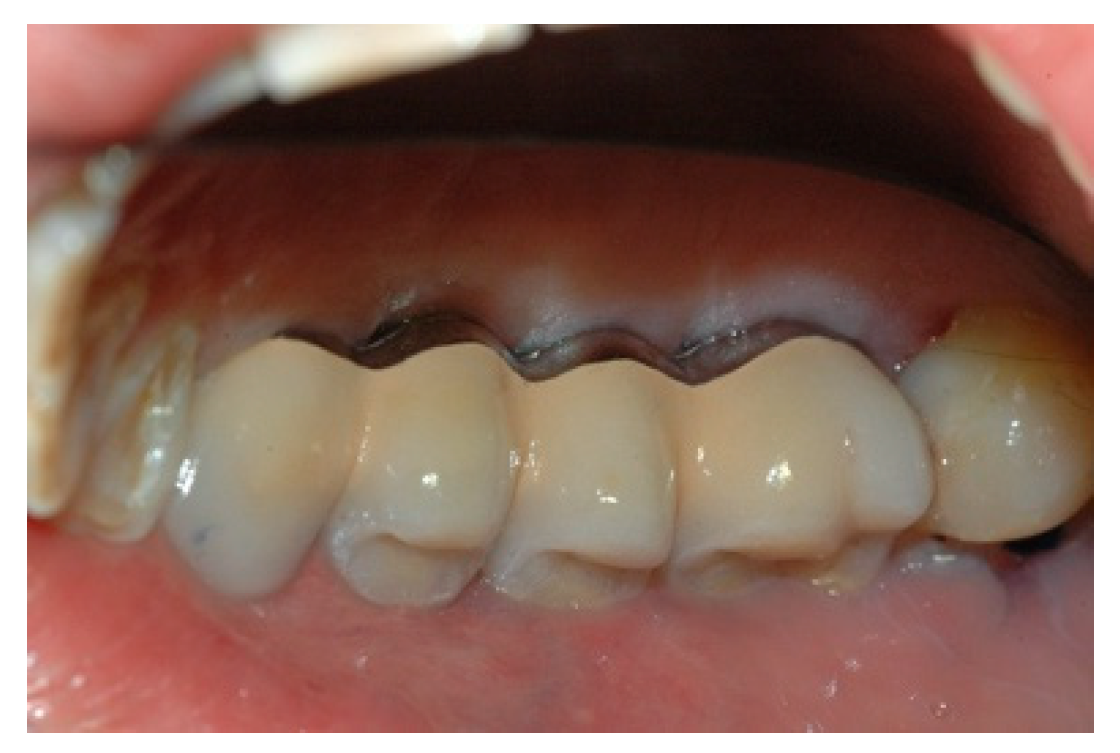

Upon positive feedback, the construction of a superstructure was carried out by performing fusion and subsequent ceramicization in the laboratory (Figure 10 and Figure 11).

Figure 10. The built superstructure.

Prosthesis 02 00023 g010

Figure 11. The built superstructure.

Prosthesis 02 00023 g011